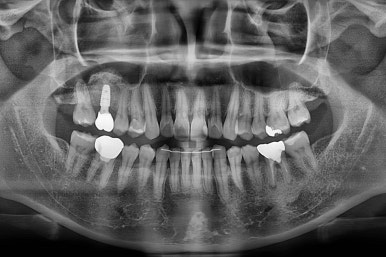

X-ray로 봤을 때 빈 공간에는 여러 가지 문제가 있었는데요.

뒷니가 쓰러졌다.

공간이 잠식 당했다.

어금니 위쪽 공기주머니가 잇몸뼈를 갉아먹으면서 잇몸뼈가 매우 얇아져있다.

진행상황을 X-ray로도 확인해 줍니다.

어금니도 원위치로 많이 갔네요.